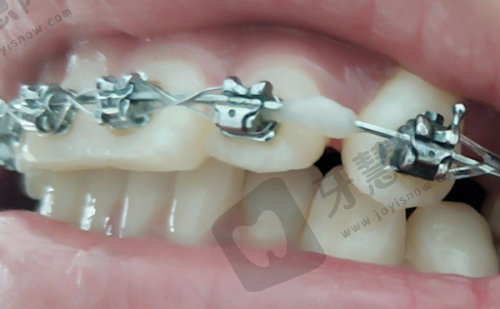

韩国uf种植体有其独特的技术特点。它具有开放螺纹,这种设计更有利于和牙槽骨的结合。其采用的Hsa表面处理,比rbm表面处理的骨形成速度快49%。这种表面处理技术能够促进骨细胞的生长和附着,加快种植体与牙槽骨的融合过程。

奥齿泰种植体的技术特点也十分突出。它采用多孔纳米氧化钛技术进行表面处理,使得种植体具有更强的生物活性、更小的排异性。这种表面处理技术能够让种植体更好地与人体组织相容,减少排异反应的发生。此外,奥齿泰种植系统独有多重微螺纹设计,增加与颌骨接触面积,无损植入设计使植入更顺利,植入后更稳定、成功几率更高。

对比两者的技术特点,韩国uf种植体在骨形成速度方面有优势,而奥齿泰种植体在生物活性、排异性以及植入稳定性和成功几率方面表现更出色。不同的技术特点适用于不同的患者需求和口腔状况。